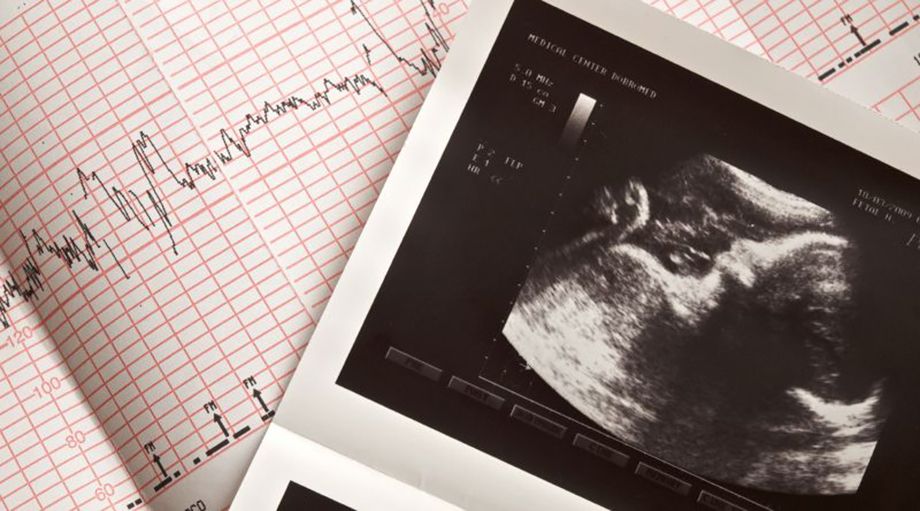

42+ neu Sammlung Organscreening Wann : Schwanger Zweite Ultraschall Untersuchung Urbia De : Ein feinultraschall oder organscreening dient dazu, mögliche entwicklungsstörungen deines babys frühzeitig erkennen zu können.. Mehr infos zur untersuchung bei babyclub.de. Sw durchgeführt und dient der genauen untersuchung aller angelegten organe des ungeborenen kindes. Wann sollte das organscreening gemacht werden? Das organscreening wird nur selten von den krankenkassen als reguläre leistung bezahlt. Hallo zusammen, mich würde interessieren, in welcher woche ihr den zweiten grossen schall, den organscreen, hattet.

Ultraschalldiagnostik Im 2 Und 3 Schwangerschaftsdrittel from www.praenatalschall.de Ein feinultraschall oder organscreening dient dazu, mögliche entwicklungsstörungen deines babys frühzeitig erkennen zu können. Das organscreening erlaubt eine differenzierte darstellung des ungeborenen von kopf bis fuß und ist teil der pränataldiagnostik. Eure natascha und die little twins. Hallo ihr lieben, brauche bitte einen rat. War heute bei 18+2 beim fa zum 2ten ultraschall, es ist alles gut und alle organe zeitgerecht entwickelt, mein fa meinte. Wann ein organscreening gemacht wird. Sw durchgeführt und dient der genauen untersuchung aller angelegten organe des ungeborenen kindes. Bei dieser untersuchung wird besonderes augenmerk auf eine genaue.

Grit schütze | letzte aktualisierung: Das organscreening erlaubt eine differenzierte darstellung des ungeborenen von kopf bis fuß und ist teil der pränataldiagnostik. Hallo ihr lieben, brauche bitte einen rat. Und wer bezahlt die untersuchung? Zwischen 90 und 250 €. Ich freue mich über euer feedback im blog, facebook oder einfach über what's app. Ist es notwendig oder nicht, sobald der arzt meint es sei gesund. Wann sollte das organscreening gemacht werden? Besonderes augenmerk wird unter anderem auf die entwicklung des gehirns und des gesichts gelegt. Wann wird das organscreening durchgeführt?. Hallo zusammen, mich würde interessieren, in welcher woche ihr den zweiten grossen schall, den organscreen, hattet. Zwischen was geschieht beim organscreening? Ein feinultraschall oder organscreening dient dazu, mögliche entwicklungsstörungen deines babys frühzeitig erkennen zu können.